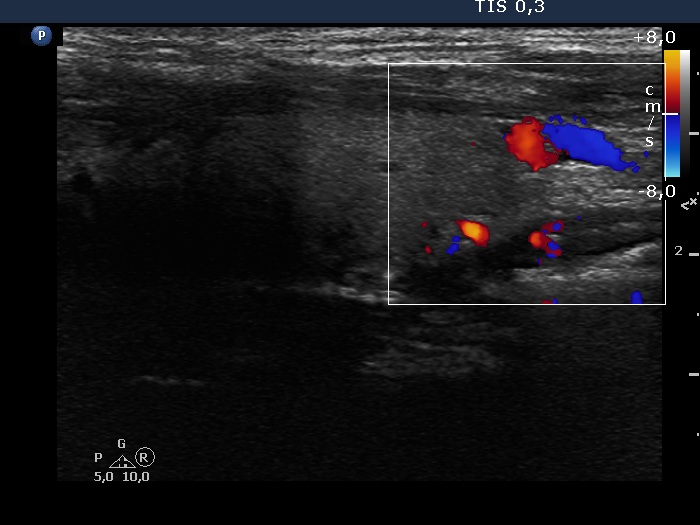

Halo sign and vascular pattern of nodules - case 971 (ultrasonographic picture 6)

Left lobe, longitudinal scan, color Doppler mode.